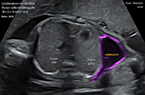

Grossesse môlaire volumineuse de 739 ml de volume Grossesse môlaire volumineuse de 739 ml de volume Grossesse môlaire volumineuse de 739 ml de volume